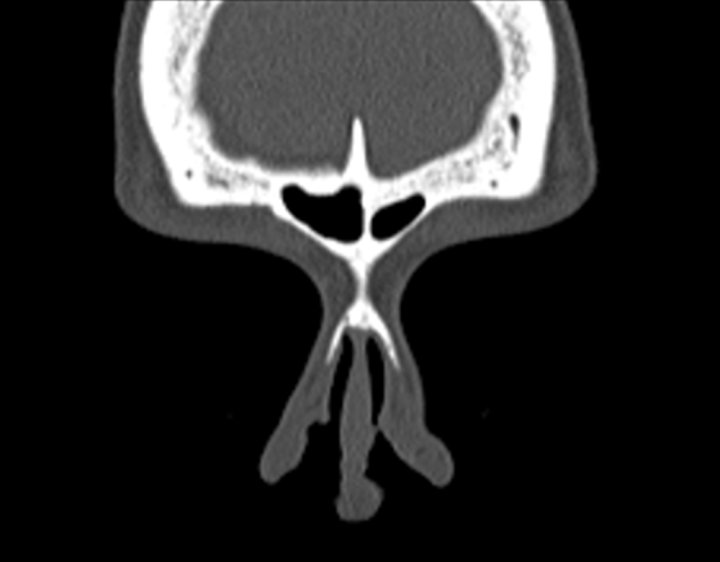

Click any image for labels.